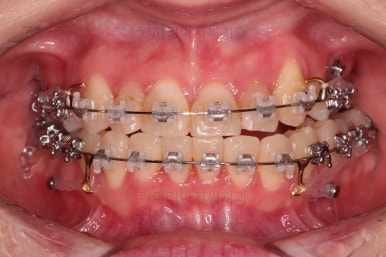

덧니를 개선하기 위해서 추가적으로 작은 어금니를 발치했고요.

이 때 발치하게 된 치아는 가장 약한 치아, 치료가 많이 되어있거나 치료가 필요한 치아 위주로 선택하게 됩니다.

아랫니는 많이 삐뚤긴 했지만 옆라인, 턱의 크기 등 모든 걸 종합적으로 판단해 비발치로 진행하기로 했습니다.

물론 윗니 이미 없었던 치아 부분은 공간을 모아서 임플란트를 하지 않도록 하는게 목표였고요.

윗니 앞니는 급한대로 신경치료 부터 진행했고, 최종 심미보철은 교정 후 미루었습니다.

공간을 줄여나가고 순차적으로 충치치료도 마무리 해갑니다.

교합이라던가 부족한 부분을 좀 더 마무리하고요.